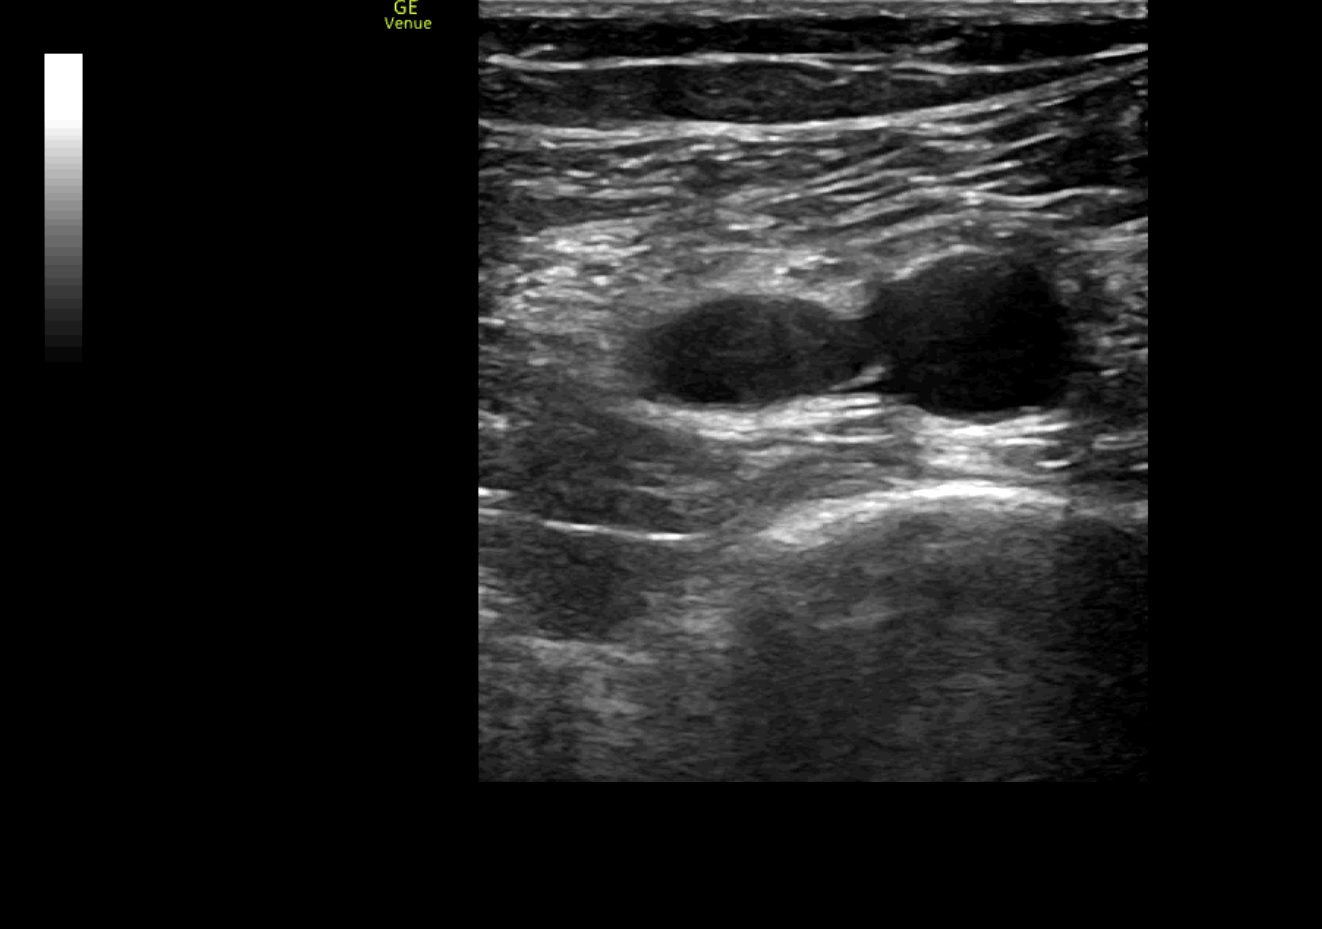

Se realiza ecografía clínica de vasos en miembros inferiores objetivándose un trombo en vena poplítea derecha y ecocardioscopia con dilatación de ventrículo derecho.